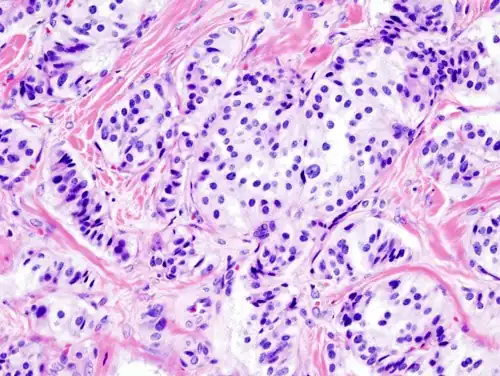

Pathology of pancreatic endocrine tumour (insulinoma).